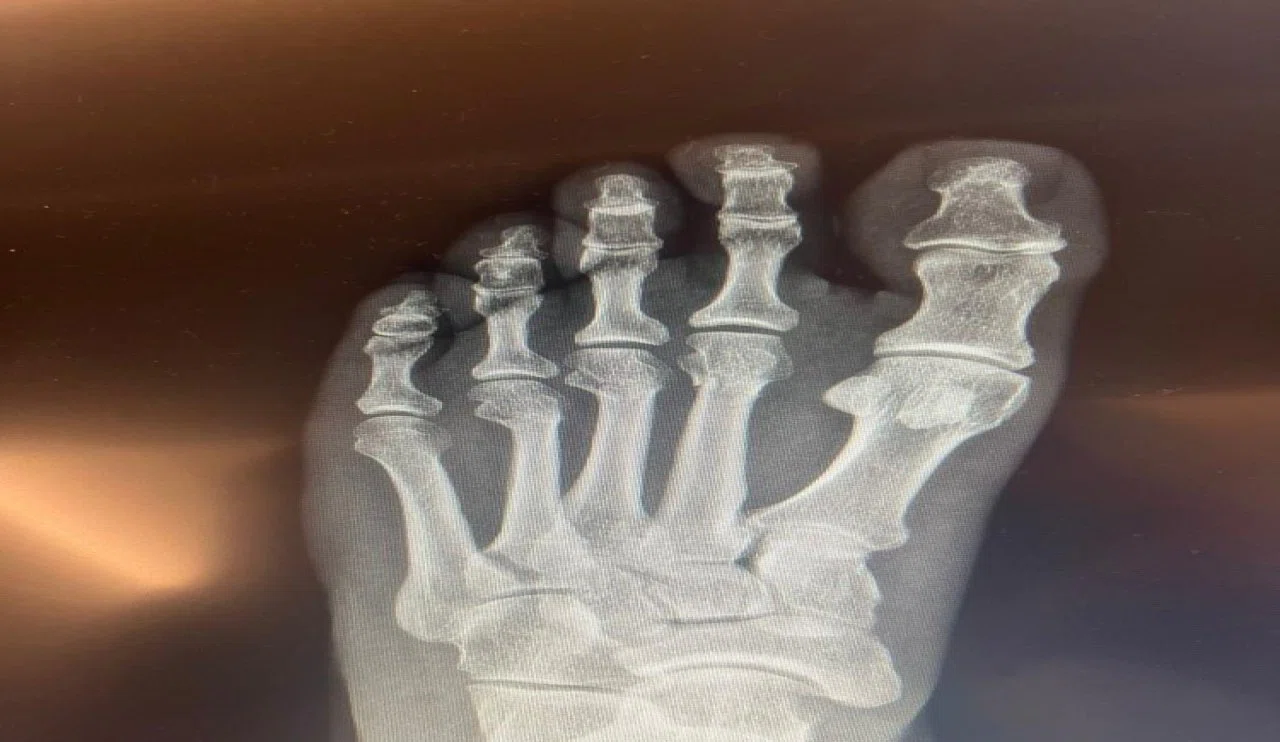

Anadolu'da Bugün Gündem Özel' den iddialara karşılık ayak röntgeni geldi!

Özel' den iddialara karşılık ayak röntgeni geldi!

Cumhuriyet Halk Partisi Genel Başkanı Özgür Özel, sosyal medyada yer alan ‘ayağından vuruldu’ iddialarına ilişkin, kırılan ayağının röntgen filmlerini paylaştı.

CHP Grup Başkanvekili Ali Mahir Başarır, geçen hafta TBMM'deki özel oturum öncesi gazetecilere yaptığı açıklamada, CHP Genel Başkanı Özgür Özel'in evde geçirdiği kaza sonucu ayağında ufak çaplı kırılma olduğunu duyurmuştu.

Özel’in ayağında oluşan kırık hakkında sosyal medyada, Özel'in ‘ayağından vurulduğu’ iddiaları yer almıştı. Özel, tartışmalara ilişkin ayağının röntgen filmlerini paylaştı.